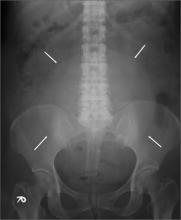

Teenager with shortness of breath and hypoxia

A 19-year-old male complaining of shortness of breath was transferred from our facility’s urgent care unit to our emergency department. He had a 2-week history of hemoptysis and vomiting, and over the previous week, he had developed mild hematemesis. His other symptoms included left thigh, flank, and upper quadrant pain; left chest pain exacerbated by exertion, light-headedness, and palpitations. He said that over the past 8 months, he’d been tired and lost some weight.

His blood pressure was 138/77 mm Hg, pulse was 142 beats per min, respiratory rate was 22 breaths per min, and oxygen saturation was 93% on room air. The physical exam revealed normal breath sounds and a diffusely tender abdomen. We ordered a chest X-ray (FIGURE).

Diagnosis: Metastatic testicular cancer

The chest x-ray showed multiple bilateral discrete nodules throughout all of the lung fields. These findings, along with the age of the patient, prompted the radiologist to suspect metastatic testicular cancer. An examination of the patient’s scrotum revealed an 11-cm mass encompassing the patient’s left testicle. When asked about the mass, the patient acknowledged that it had been there for about 8 months.

Diagnosis usually is made clinically and pathologically at resection. Left untreated, testicular cancer spreads via the lymphatic system to the retroperitoneal lymph nodes and through the bloodstream to the lungs (predominantly),4 as well as to bone, the liver, and the brain. Metastatic testicular cancer to the lungs, liver, and retroperitoneum occurs in advanced disease and has a poor prognosis.4,5

The differential diagnosis includes atypical pneumonia, septic emboli (ie, endocarditis or Lemierre’s syndrome), or sarcoidosis. Patients with atypical pneumonia often present with a cough, fever, and malaise. Patients with septic emboli will have an x-ray that looks similar to that of our patient. Their signs and symptoms will include malaise, shortness of breath, hypoxia, tachycardia, and tachypnea. Risk factors and physical exam findings might include a history of intravenous drug abuse (endocarditis) or deep tissue neck infection (Lemierre’s syndrome). Sarcoidosis can be a challenging diagnosis without further study.